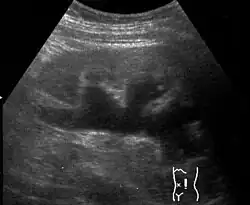

Untersuchungen, die zur Abklärung einer Hydronephrose eingesetzt werden, sind Sonografie, intravenöse Pyelographie, Miktionszystourethrographie und Szintigraphie (zur Beurteilung der Nierenrestfunktion).